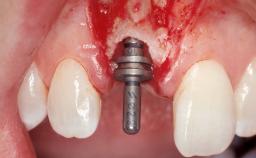

Immediate Flapless Placement of an Implant in a Maxillary Left Central Incisor Site

A 42-year-old female patient was referred to our clinic at the School of Dentistry of the University of São Paulo in November 2004, presenting a deficient restoration in the upper left central incisor. The clinical examination revealed no gingival retraction or any signs of gingival inflammation and, therefore, previous periodontal treatment was not considered. The patient presented a high lip line at full smile and a thin tissue biotype. This combination characterized a high-risk situation from an anatomic point of view, which required careful preoperative planning and cautious surgical execution.